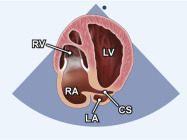

| 2.18. Mặt cắt 4 buồng từ mỏm nghiêng ghi hình xoang vành |

||||||||

|

|

Cửa sổ siêu âm từ mỏm tim

Mặt cắt 4 buồng Từ mặt cắt 4 buồng từ mỏm, nghiêng chùm siêu âm ra sau để ghi hình xoang vành. |

Xoang vành (CS) Nhĩ phải (RA) Thất phải (RV) Thất trái (LV) Nhĩ trái (LA) |

|||||